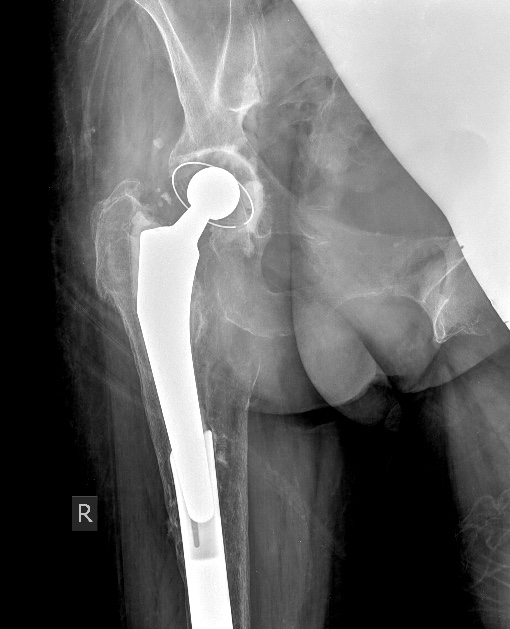

У Марининой получилось не совсем идеально - ножка не села в эти канавки.

Картинка (2 года в приложении) - видно, что пропил в гвозде не по центру

ножки. С полностью эллиптическим пазом под ножку этого не могло произойти,

гвоздь "автоматически" поворачивался (или ножка поворачивалась)

соответственно плоскости ножки.

Name: Маринина 2 года.jpg